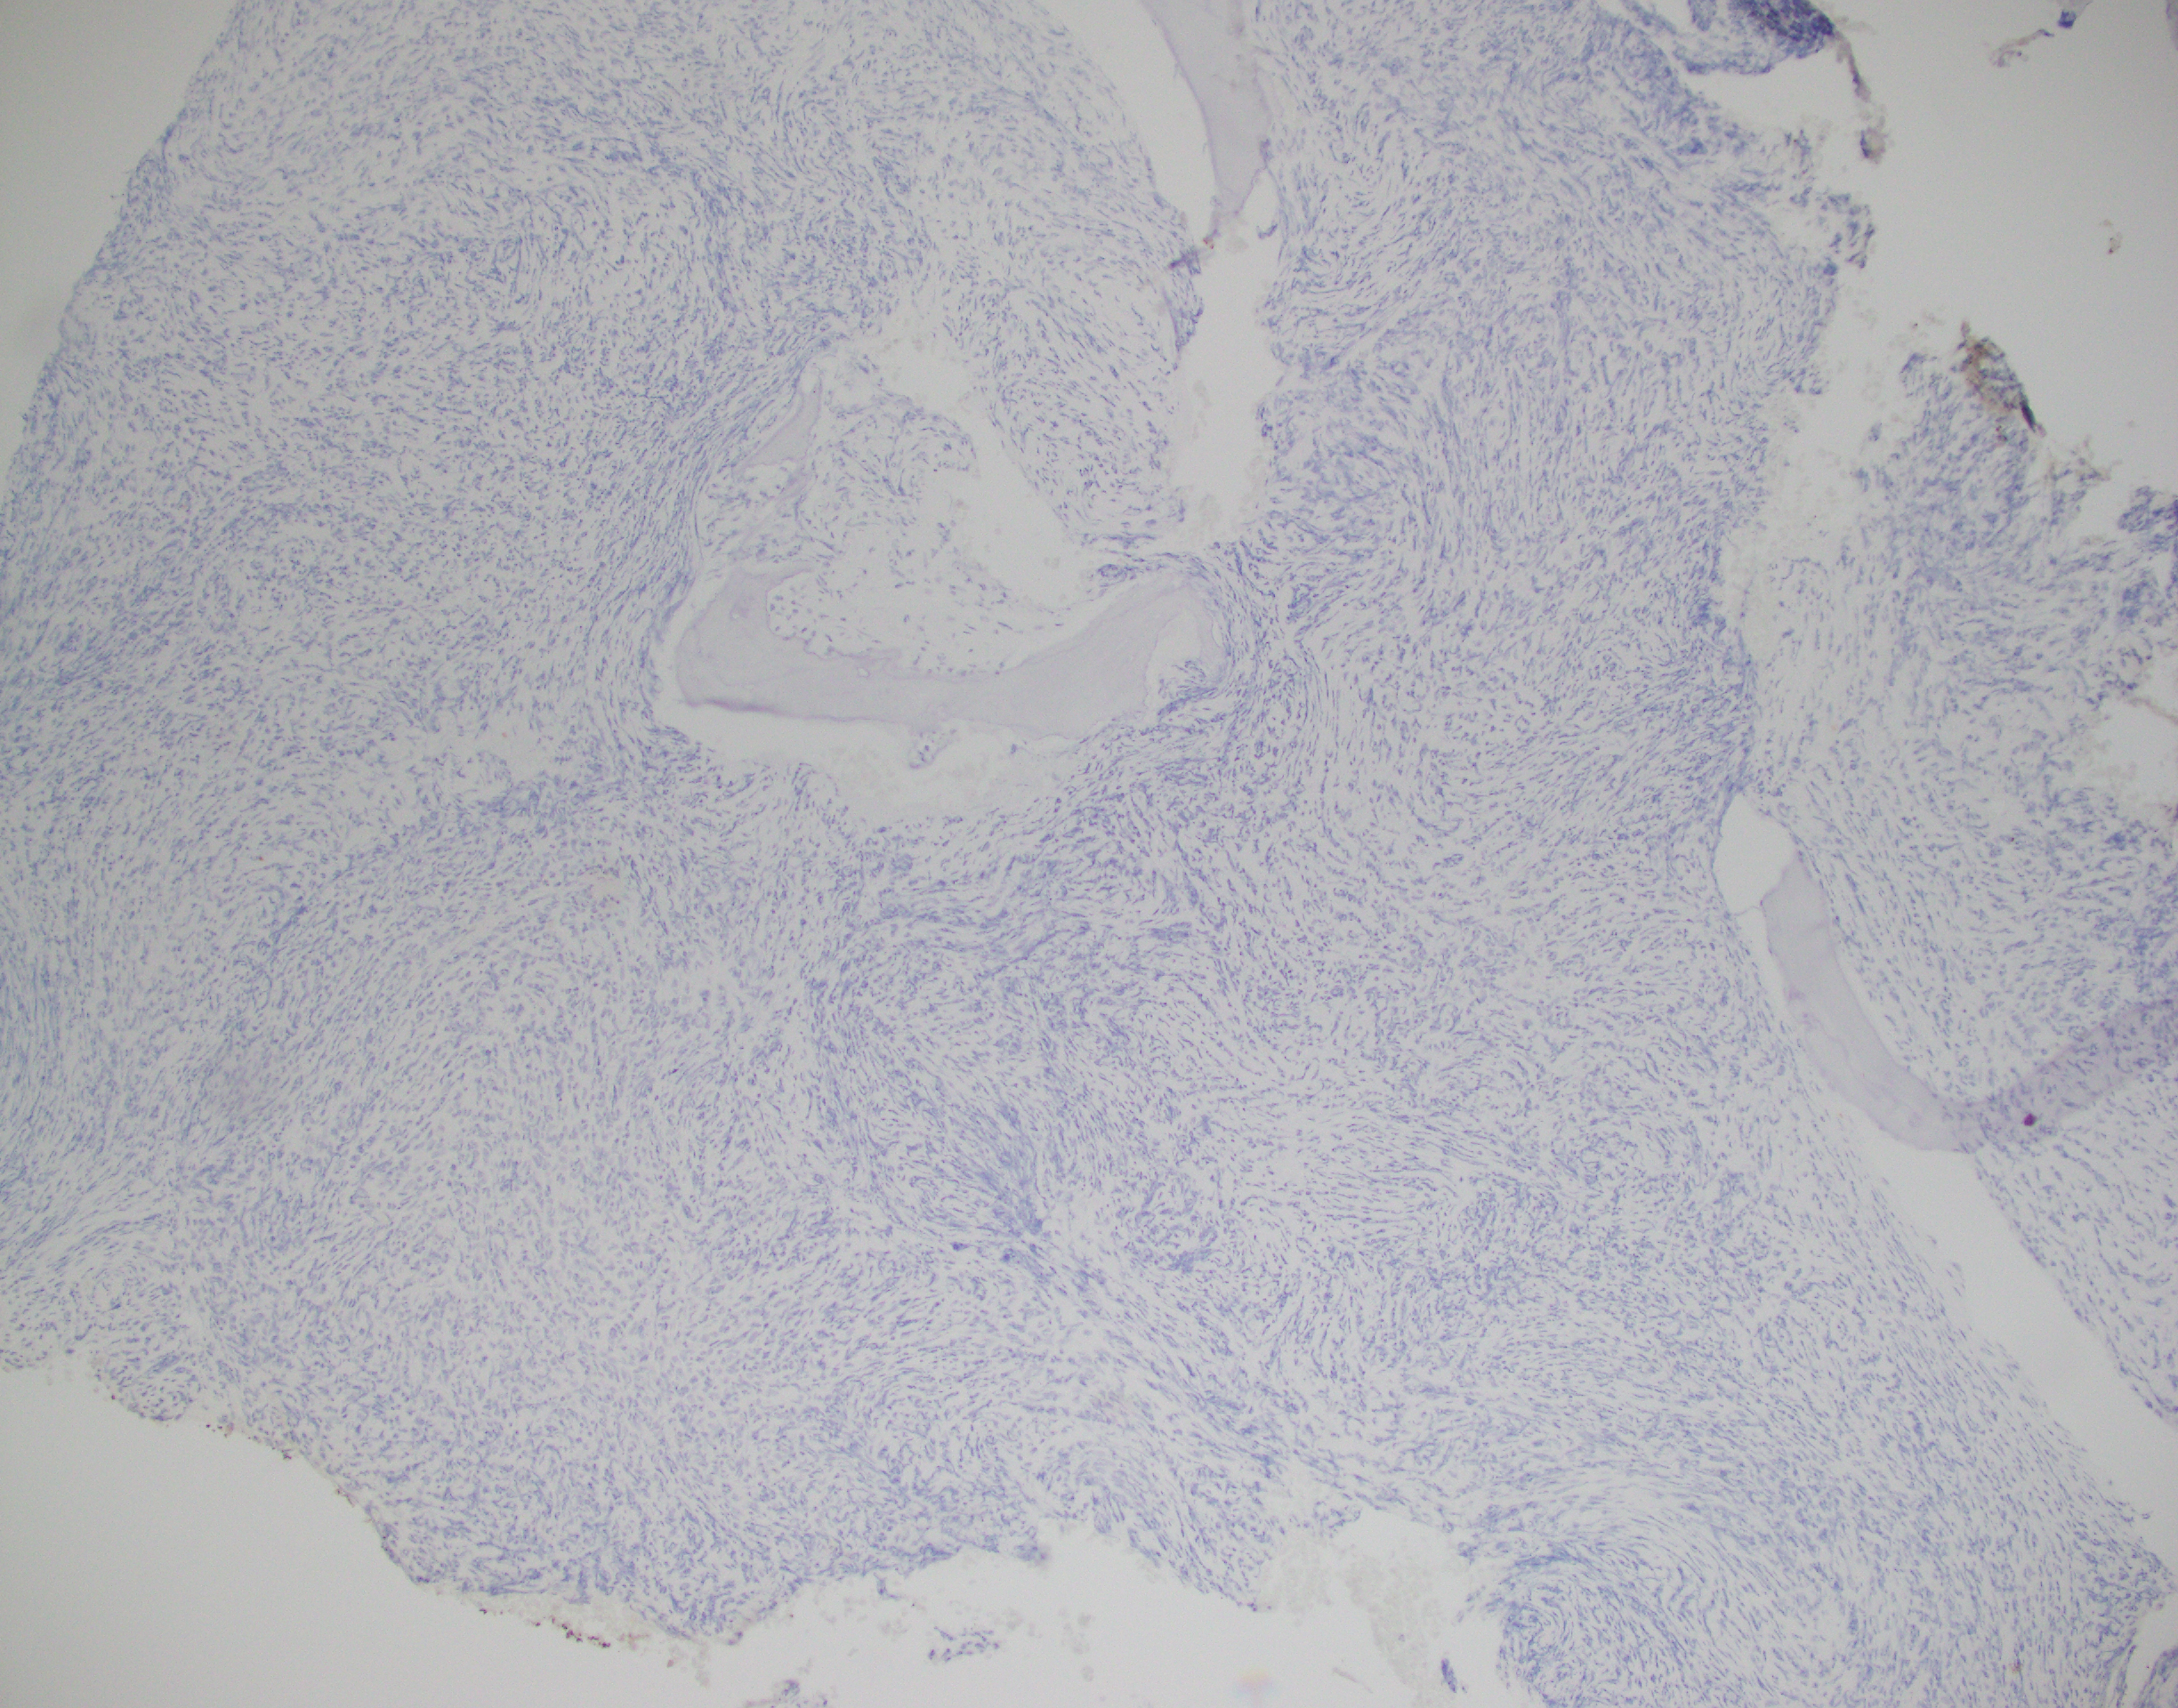

Essentially, this patient was found to have Li-Fraumeni after the second manifestation of an acute sarcoma—the first being osteosarcoma in her teenage years and the second breast cancer in her 30s. Both cancer diagnoses were treated accordingly, and this patient was going through routine work-up for anemia before being referred to the Mayo Clinic. By the time the patient reached there, the clinical investigation included a battery of testing for causes of anemia—all within normal limits—so a bone marrow examination was performed which revealed a significant, though not acute (<20% blasts), myelodysplastic process. A follow-up in-house bone marrow collection revealed hypercellular marrow, now in acute myeloid proliferation, with abnormal myeloid cell maturation and very complex cytogenetics. She had a very complex karyotype and several detectable mutations which were consistent with the WHO’s classification and description of therapy-related myeloid neoplasm as a sequale to the treatments she received for her prior cancers. In the setting of a patient with LFS, it is almost impossible to avoid malignancy. The following slides are a (very abridged) summary taken from my presentation of this patient’s case:

In a case report from 2017 I discussed a patient who had bilateral lung nodules several years after being treated for breast carcinoma. It was initially thought to be relapse but was later correctly diagnosed as de novo peripheral T-cell lymphoma (PTCL). This could have very well been the same clinical scenario, with a different cell lineage. The lesson gleaned here is the same as those ASH/CAP guidelines: stay organized, consistent, and purposeful with your testing and investigation. What came down to a few immunohistochemical markers in this PTCL case could make all the difference in another case. Missing the clinical history and specific genetic mutations present in this LFS/AML patient could have led to a diagnosis of a myelodysplasia related AML instead of a therapy-related one, especially in the setting of such a severe germline pre-disposition.